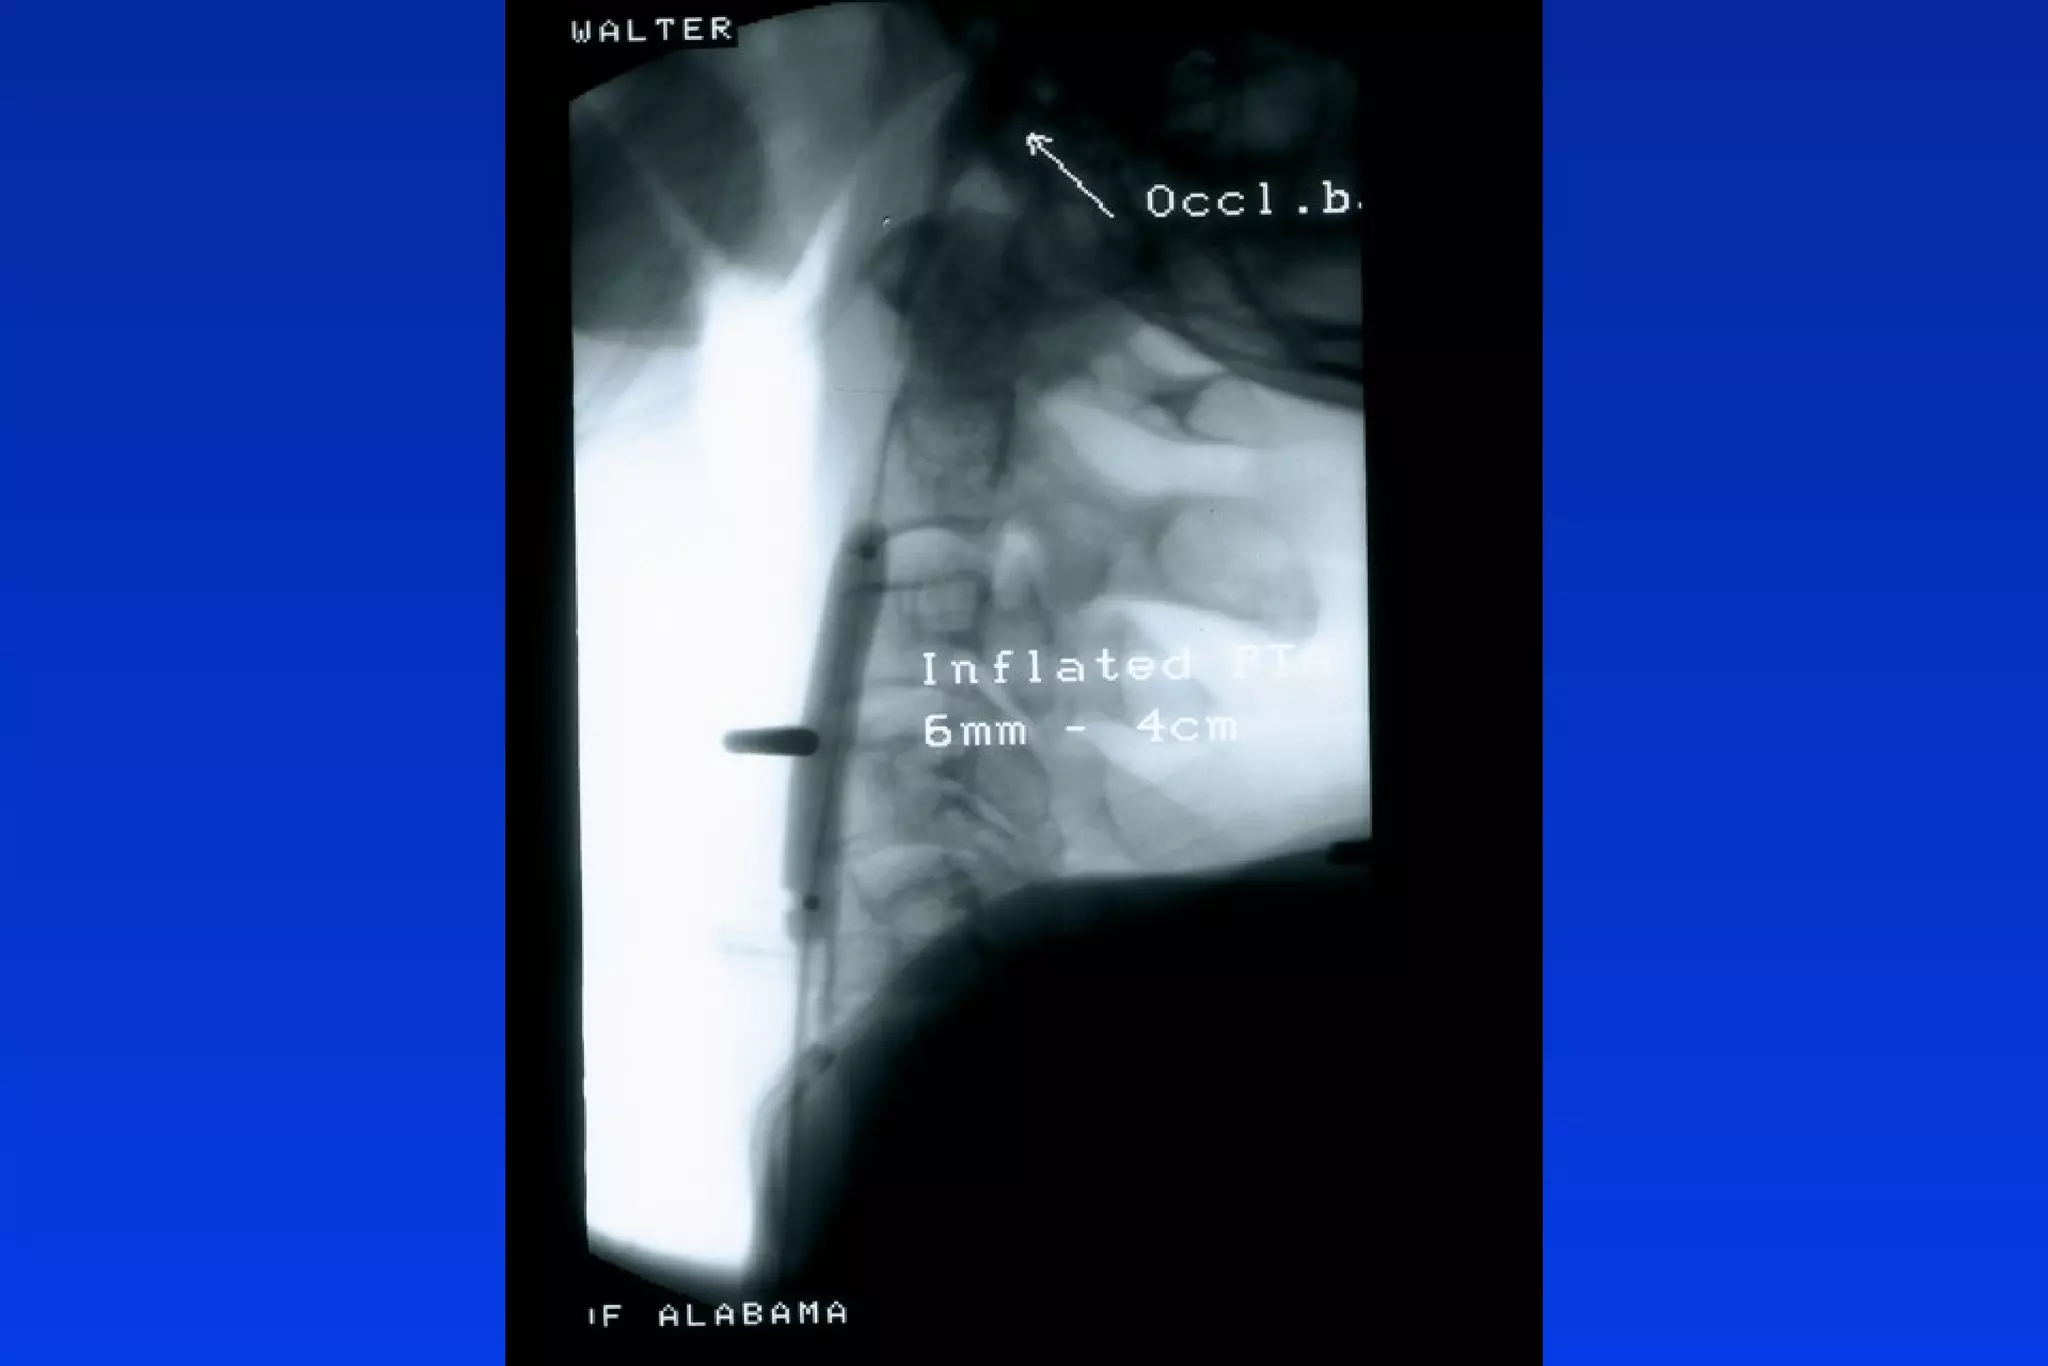

Transcranial Doppler (TCD)

MIDDLE

CEREBRAL

ARTERY

VELOCITY

CM/SEC

EMBOLI

BALLOON INFLATED DEFLATED